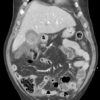

Vỡ túi mật

» Thông tin: Nam giới – 80 tuổi.

» Lâm sàng: Chấn thương.